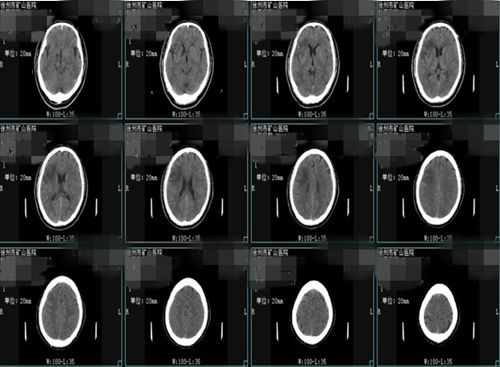

患者陈先生,55岁,2018年11月22日下午14:32分因突发口角歪斜、右侧额颞部头痛6小时入住徐州市矿山医院神经内科。头颅CT示:右侧额颞叶脑梗死;头颅CTA示:右侧颈内动脉起始部闭塞,左侧颈内动脉起始部重度狭窄(80%以上)。张晓玲主任综合患者病情,诊断其为1、急性脑梗死;2、高血压病;3、II型糖尿病。

头颅MRI

术后CT